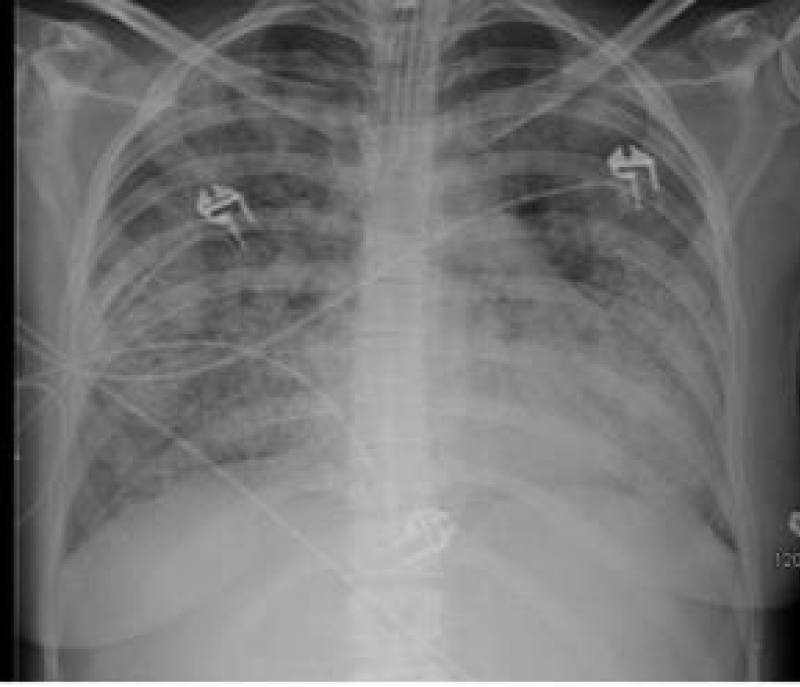

A 29 year old serving soldier was admitted with complains of fever, pain abdomen, hemoptysis, bodyache and dark coloured urine since 03 days. On admission patient was tachypneic and hypotensive. Blood investigations revealed decrease hemoglobin and platelet count. pANCA came out to be positive. CT scan was suggestive of bilateral nodular densities and x ray showed bilateral fluffy opacities. Despite management with oxygenation, iv fluids and iv antibiotics, there was no improvement in his symptoms and his condition further deteriorated. Bronchoscopy revealed diffuse bronchoalveolar hemorrhage. Biochemical evaluation revealed deranged kidney and liver function test. Patient on ventilation developed bradycardia, hypotension and desaturation. On examination blood pressure was not recordable, carotid pulse was not recordable, CPR was started and patient was declared dead at 1215hrs on 30 Oct 2020 Figures 1,2.

Figure 2: CT scan shows multiple nodular densities.